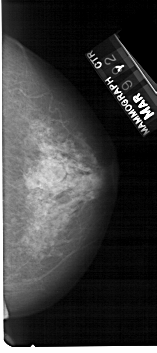

ics_version 1.0 filename A-1317-1 DATE_OF_STUDY 9 3 1992 PATIENT_AGE 68 FILM FILM_TYPE REGULAR DENSITY 4 DATE_DIGITIZED 28 7 1998 DIGITIZER HOWTEK 43.5 SEQUENCE LEFT_CC LINES 5146 PIXELS_PER_LINE 2236 BITS_PER_PIXEL 12 RESOLUTION 43.5 OVERLAY LEFT_MLO LINES 5491 PIXELS_PER_LINE 2611 BITS_PER_PIXEL 12 RESOLUTION 43.5 OVERLAY RIGHT_CC LINES 5281 PIXELS_PER_LINE 2341 BITS_PER_PIXEL 12 RESOLUTION 43.5 NON_OVERLAY RIGHT_MLO LINES 5491 PIXELS_PER_LINE 2911 BITS_PER_PIXEL 12 RESOLUTION 43.5 NON_OVERLAY |